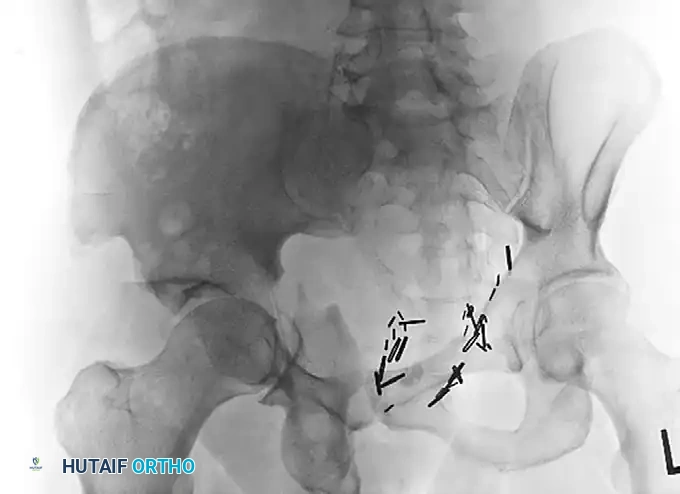

Preoperative Judet oblique radiograph highlighting the extent of posterior column displacement and wall comminution, indicating a poor prognosis for isolated joint preservation.